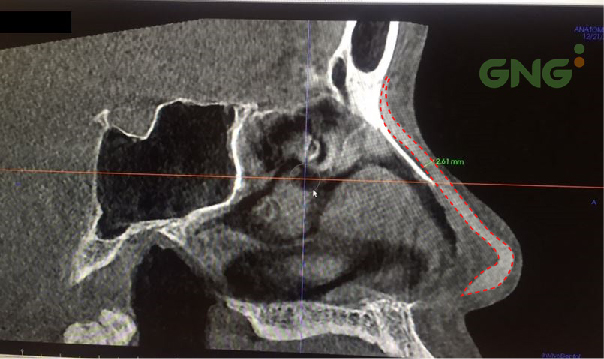

After an X-Ray and CT scan and face to face consultation with ours doctors, the doctor and you will decide which method is best for you and your nose based on your nose structure, skin type, and ideal nose type.